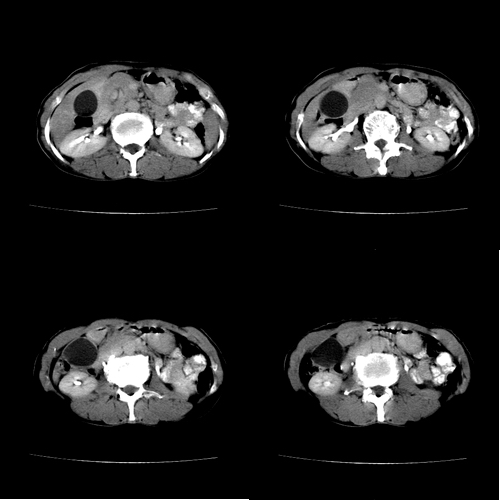

患者 女 60岁,曾多年胆结石及胆管结石,今行ct复查,非常经典.现上传,请讨论.

典型的胆总管铸型结石。

支持胆总管结石。胆囊增大受压,肝内胆管及胰腺管无明显扩张。很有意思的病例,能有冠、矢状重建图像观察就更好了。

相当漂亮的“总胆管(铸型)结石”。多谢楼主!

结石这么大,肝内胆管扩张不明显,胆囊扩张明显。能否考虑结石位于胆囊管内并外压总肝管?

胆总管内多层同心圆样结石,确属精典,谢谢卜一老师!